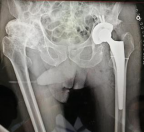

2、髋、膝关节置换手术经验丰富,完善的快速康复方案,手术更微创,无需输血,有效纠正畸形、消除疼痛,可迅速下地,恢复正常活动功能。

髋关节置换